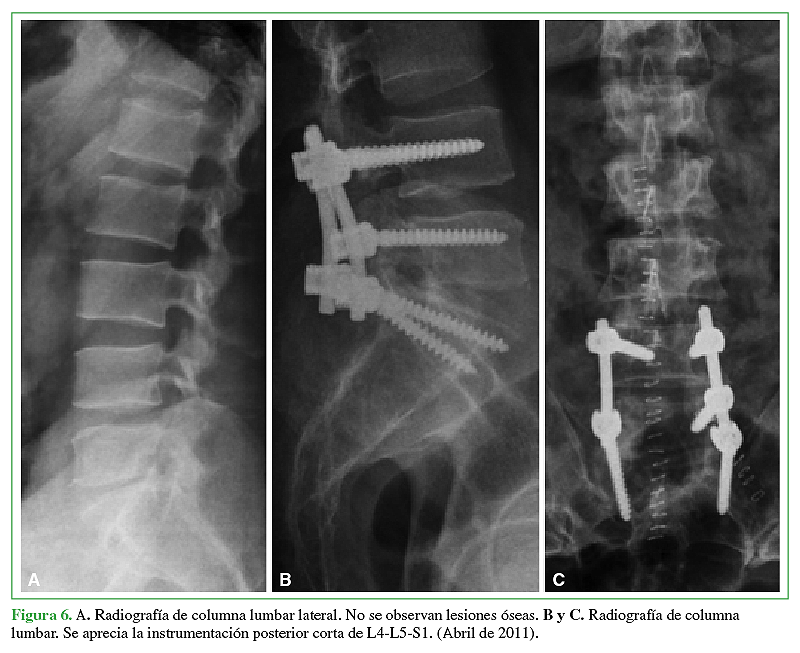

La hidatidosis es una enfermedad causada por el estado larval del platelminto Echinococcus, siendo la especie más prevalente Echinococcus granulosus. Es endémica Eurasia, Africa, Australia y Sudamérica. En Chile tiene una incidencia notificada de 2,1 casos por 100.000 habitantes y a pesar de que está asociada a las zonas ganaderas del sur de Chile, se presenta a lo largo de todo el territorio debido al desplazamiento de la población y su largo período de incubación. Se caracteriza por la presencia de un quiste habitualmente a nivel hepático (75%) o pulmonar (15%). La afectación de otros territorios es menos frecuente y el compromiso óseo es una rareza que no supera el 1 a 2,5%, ya sea en el tejido trabecular o canal medular. El tratamiento por lo general es médico-quirúrgico con resultados clínicos dispares debido a alta tasa de recurrencias y secuelas. La experiencia en el manejo de pacientes afectados con hidatidosis intrarraquídea es limitada debido a su baja frecuencia. Por ello quisimos reportar 2 casos observados en nuestro centro y analizar su manejo.Descargas